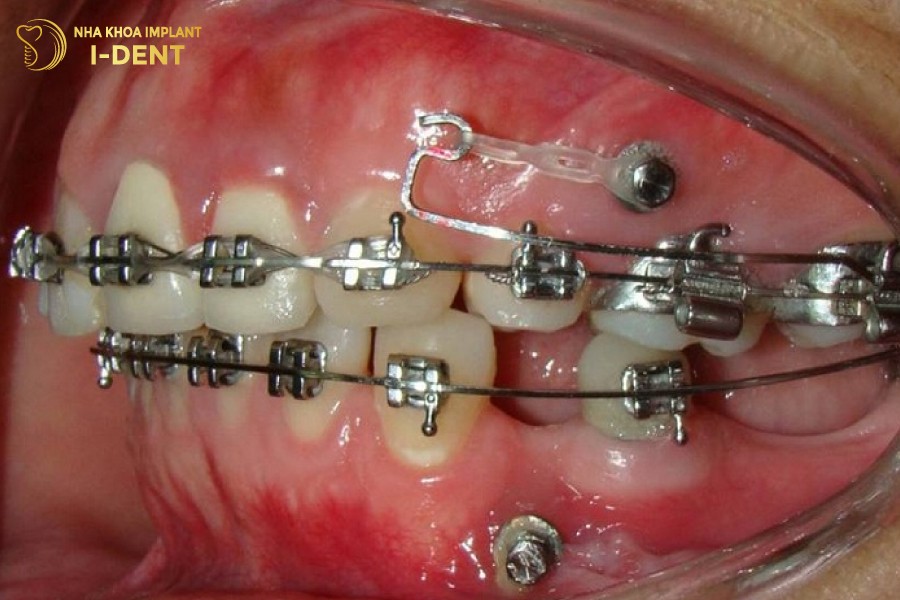

3. Phương pháp khắc phục niềng răng bị tiêu xương

Trong trường hợp bị chân xương khi niềng, điều đầu tiên bạn cần làm chính là đến gặp bác sĩ. Bác sĩ sẽ tiến hành đánh giá trực tiếp để xác định mức độ tiêu xương và đề xuất phương pháp khắc phục thích hợp. Có thể sử dụng cách tiếp cận độc lập hoặc kết hợp:

- Ghép xương hàm: Phương pháp này thường sử dụng xương nhân tạo hoặc xương từ cơ thể để ghép vào vùng xương bị tiêu. Khoảng thời gian sau, xương sẽ tái tạo, giúp phục hồi và bảo tồn xương.

- Nâng xoang hàm: Đối với trường hợp xương hàm suy giảm và dần mất độ cao, nâng xoang trở thành lựa chọn. Quy trình có thể là nâng xoang kín hoặc mở, có thể kết hợp cùng phương pháp ghép xương.

Nâng xoang hàm khi tiêu chân răng